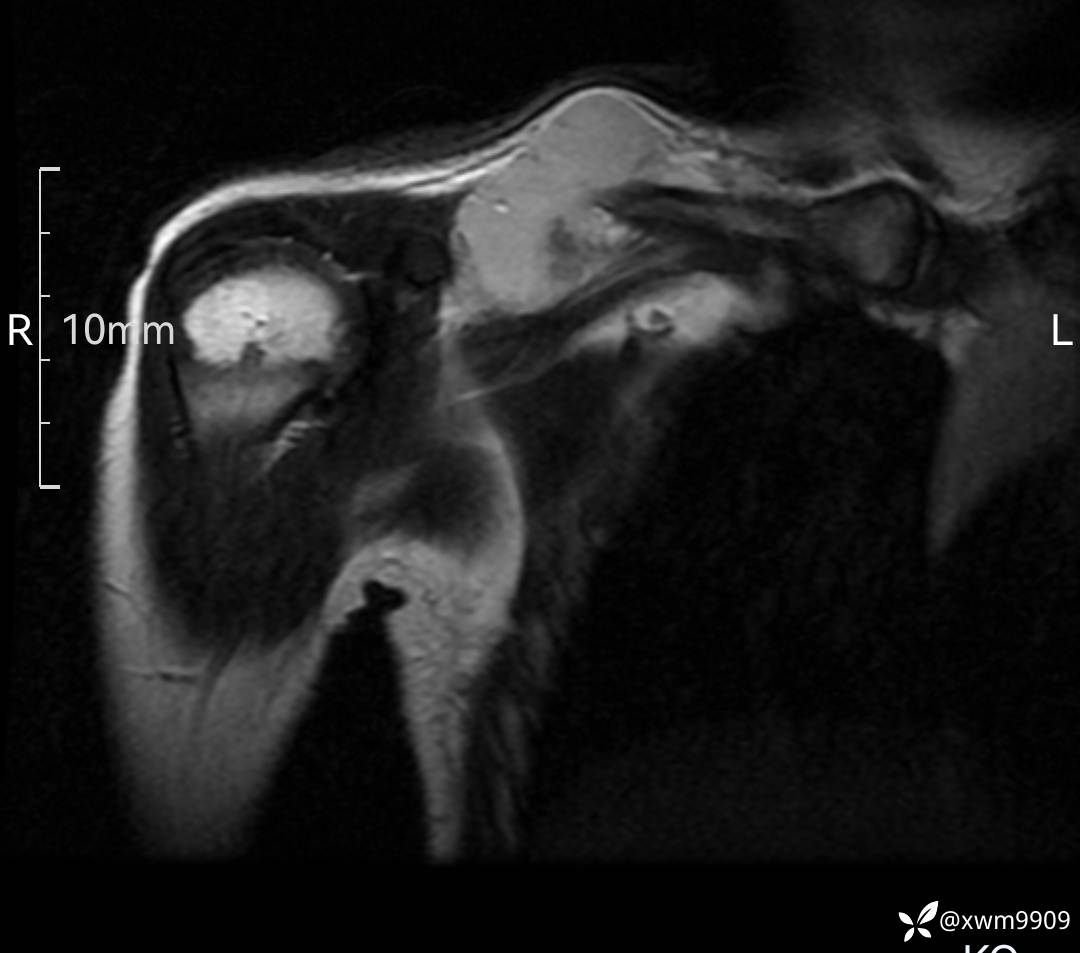

DR:

CT:

2、CT、MR肿块内可见液-液平面,常见有哪些疾病。

3、如何定性、定病?